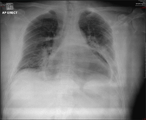

Anterior mediastinal teratoma with pericardial effusion. Rare presentation

Moaath Al Smady and others

Journal of Surgical Case Reports, Volume 2019, Issue 5, May 2019, rjz136, https://doi.org/10.1093/jscr/rjz136